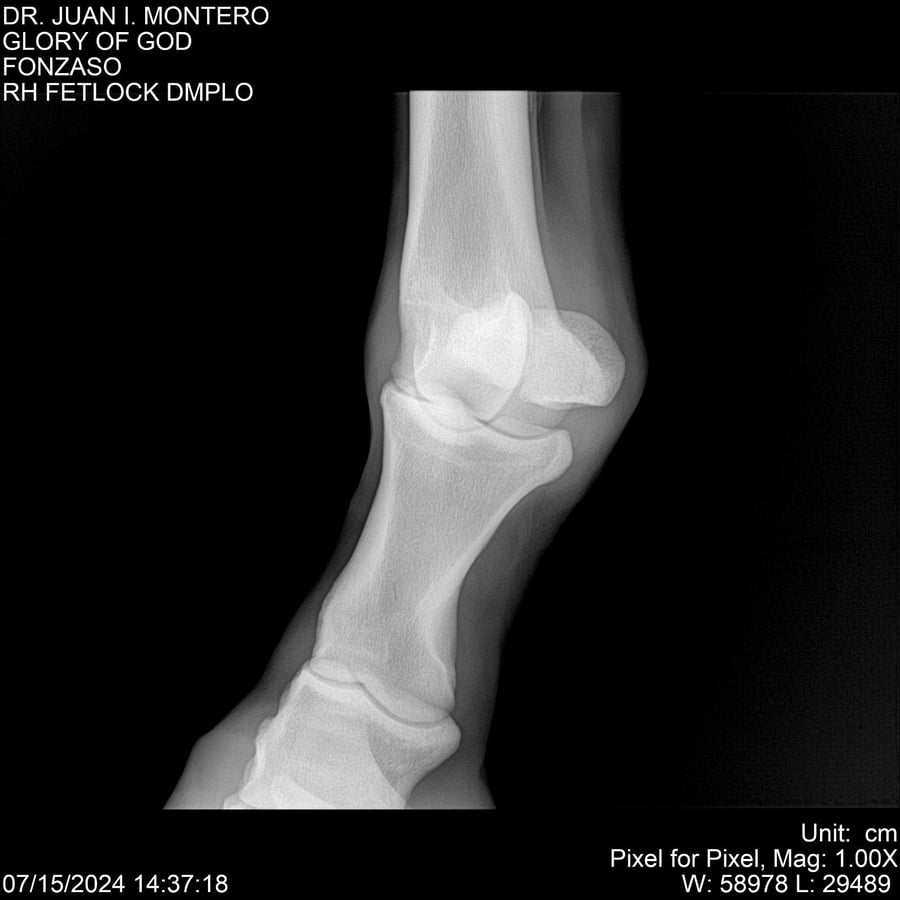

LOTE 10, GLORY OF GOD 🔥 🔥 🔥 Lote Anterior Volver al remate Lote Siguiente Ficha Contacto Montevideo - Ficha del Lote Identificador: #281389 Categoría: Yeguarizos Montevideo - 115 Visualizaciones ClicData Contacto Empresa: Abelenda N. R., Walter Hugo Nombre*: Teléfono* : E-mail* : Mensaje Enviar Registrese gratis Este contenido Exclusivo está disponible sólo para usuarios registrados Ingresar